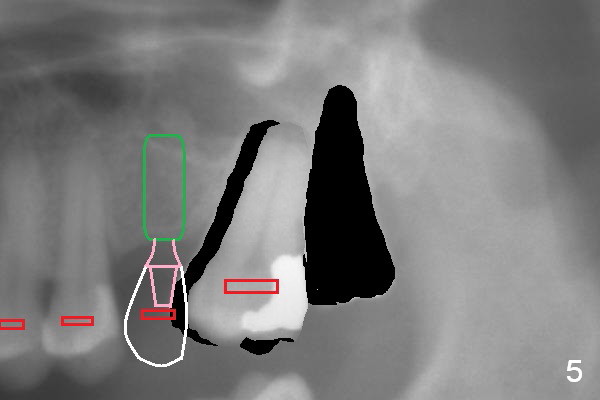

When the tooth #15 is distalized (Fig.3), place an implant at #14 (Fig.4 green), parallel to the tooth #13 and extract #16 (black). When the implant osteointegrates, place an abutment (Fig.5 pink), provisional (white) and bracket at #14. The implant is used as an anchorage to further distalize #15 until the latter reaches the normal position (Fig.6). CT study shows how much the tooth movement is needed prior to implantation.